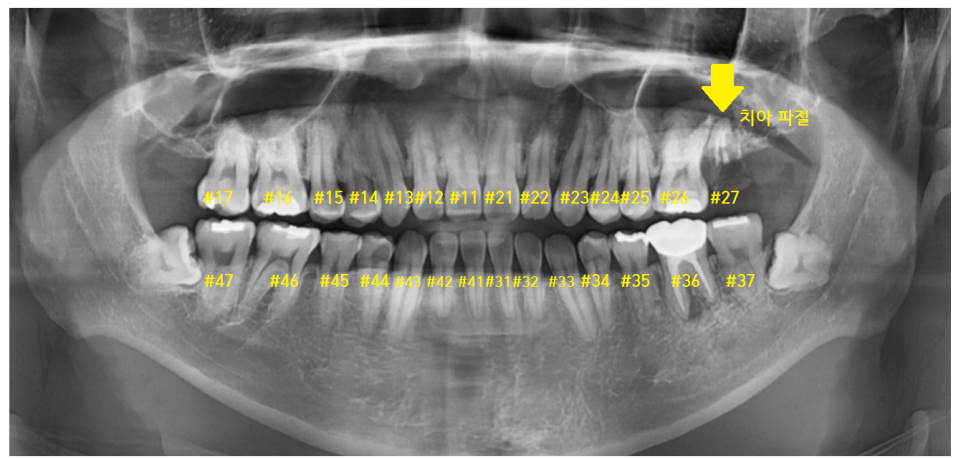

23.11.04

#27 맨 끝에 치아가 부러졌네요~

발치가 필요합니다.

구강 내 사진에서도 이가 한 개가 없죠~?

교합되는 사진을 보겠습니다.

#27 왼쪽 맨 끝 치아가 상실

#47 왼쪽 아래 맨 끝 치아가 물리는 게 없네요~

이럴 경우 맞닿은 치아가 없어서

아래 치아가 위로 쑥쑥 올라오게 됩니다.

자연치아의 손상을 방지하기 위해서라도

임플란트가 필요합니다.

24.02.22

아래 어금니를 지키기 위해서

발치 후 암사동 치과에서 임플란트를 식립하셨습니다.